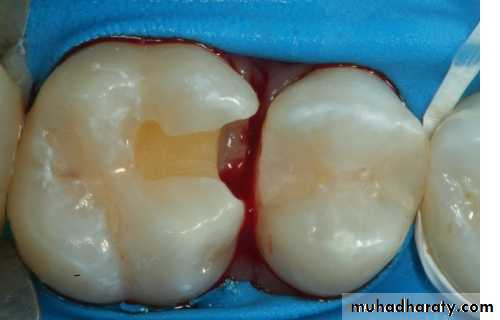

Class II cavity preparation

Occlusal outline form (occlusal step)

• The occlusal outline form of a Class II tooth preparation for amalgam is similar to that for the Class I tooth preparation.Proximal outline form (proximal box)

Box-only preparation

When restoring a small, cavitated, proximal lesion in a tooth with neither occlusal fissures nor a previously inserted occlusal restoration, a proximal box preparation without an occlusal step has been recommended.To maximize retention, preparations with facial and lingual walls that almost oppose each other are recommended.

As in the typical preparation, the facial and lingual proximal walls converge occlusally Retention locks are necessary in box-only preparations .